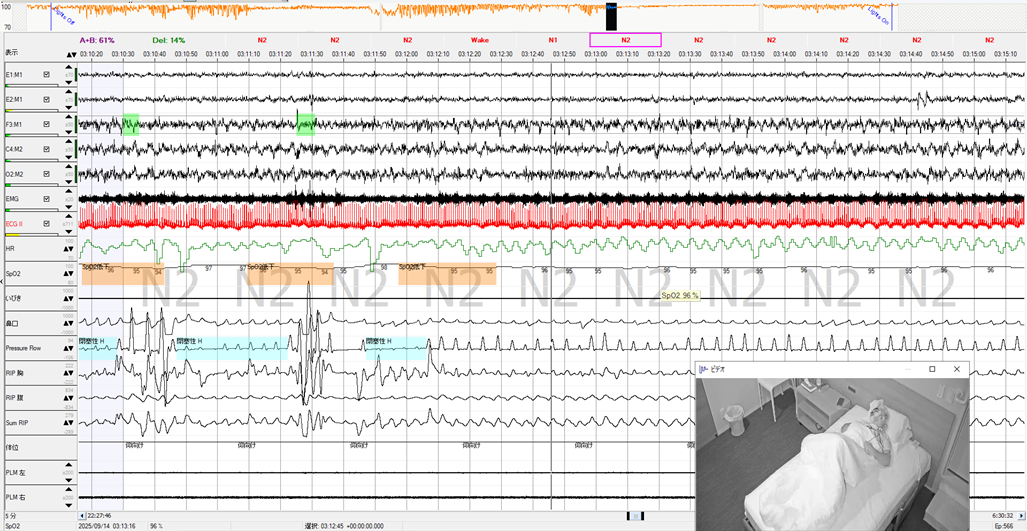

BMI低値で側臥位就寝にもかかわらず、重症の無呼吸を認めた高齢女性

70歳台 女性 身長:160㎝ 体重:51kg BMI:19.9 ESS:4無呼吸といびきを主訴に来院されました。小学生の頃にアデノイド肥大、15歳ころからいびきの指摘があるそうです。熟眠感の欠如と起床時の口渇、トイレ覚醒2回とのことで、簡易検査を施行、REI=18.1、最低SpO2=80%で、診断PSGを行いました。その結果、AHI=59.9回/時間と重症…